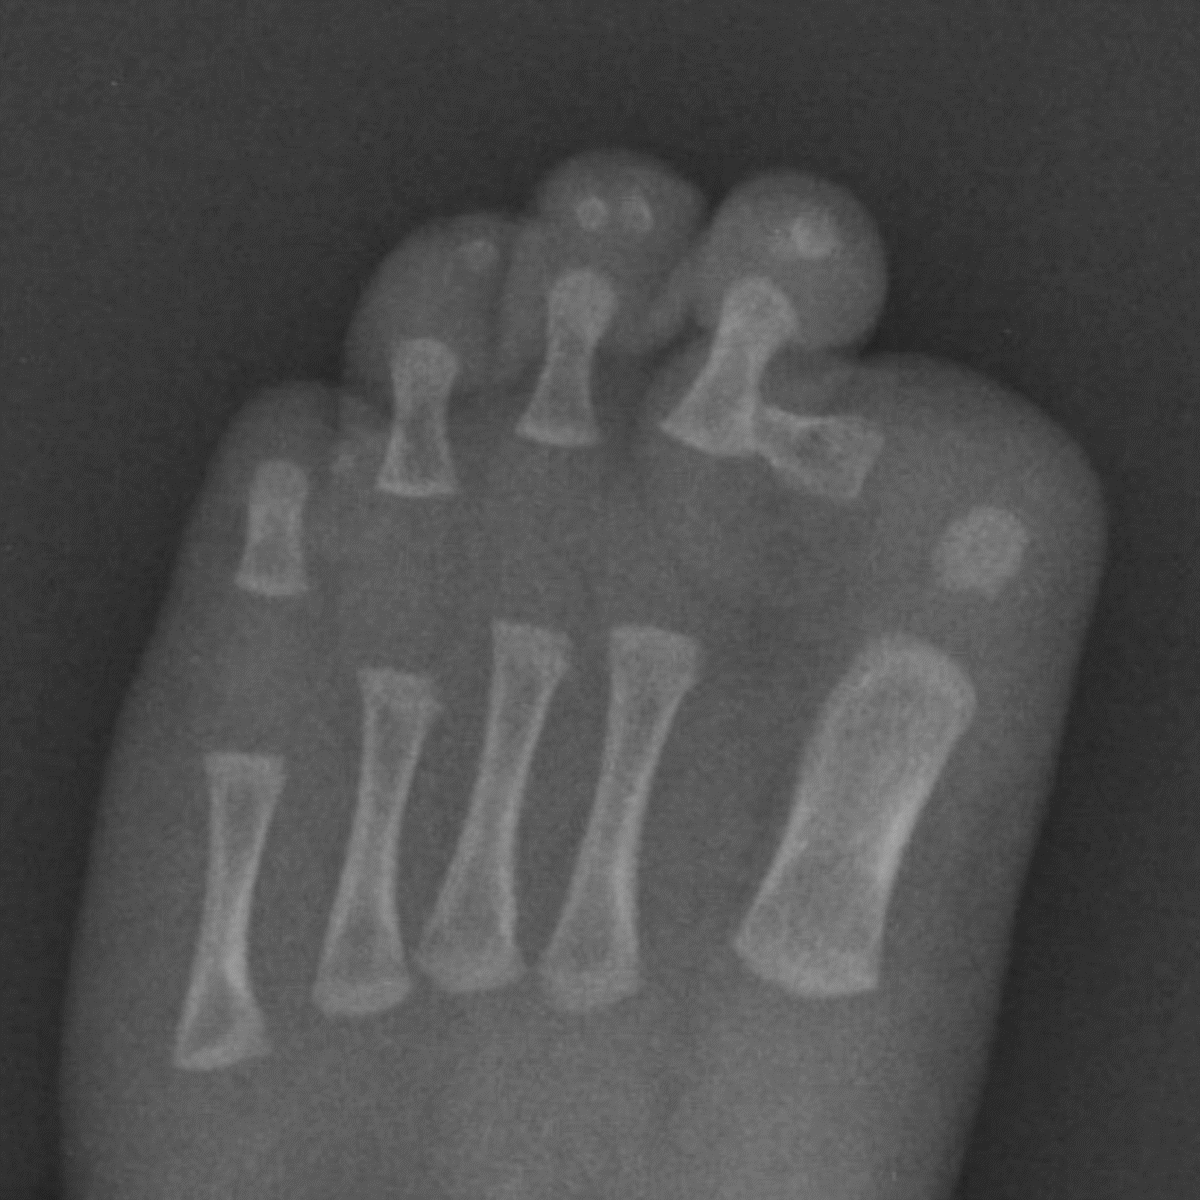

One of the key features of FOP is the shortened, turned in or missing big toes. The ‘FOP toes’ are usually visible at birth and can be noted from a quick, visual check. Babies who present with these toes are often misdiagnosed as having ‘baby bunions’ or hallux valgus. An X-ray of FOP toes can often show several very specific abnormalities, ranging from shortening, malformation or a missing joint in the great toe. Babies with FOP can also present with shortened thumbs, which also may be missing a joint.